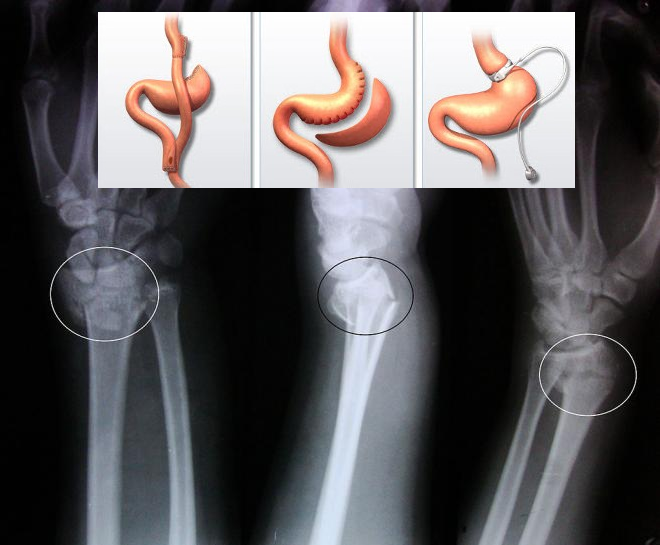

Группа исследователей из Национального университета Тайваня (Nationa lTaiwan University) под руководством Куо-Чина Хуанга (Kuo-Chin Huang) выяснила, что бариатрические операции негативно влияют на состояние костей, повышая риск развития переломов. Исследователи отмечают, что за последнее десятилетие подобные операции стали проводить в 7 раз чаще.

Авторы изучили данные о здоровье 2064 пациентов, которым в период с 2001 по 2009 год была сделана бариатрическая операция. Также они проанализировали информацию о состоянии 5027 людей, страдающих ожирением, которым операция не проводилась. Оказалось, что у тех, кто перенес операцию, риск возникновения переломов в течение пяти лет после нее был увеличен на 21%.

Переломы чаще встречались у тех, кто подвергался мальабсорбтивным операциям, предотвращающим усвоение пищи. У таких пациентов вероятность появления переломов увеличивалась на 47%, этот показатель оставался высоким в течение 12 лет после операции. Чаще всего люди ломали лучевые, локтевые, плечевые кости, а также бедренные и берцовые.

Известно, что бариатрические операции снижают вероятность развития диабета 2 типа и гипертонии. Учитывая полученные результаты, стоит помнить о том, что их проведение негативно влияет на состояние костей, подчеркивают авторы. Врачам стоит назначать своим пациентам витамин Д и кальций, чтобы укрепить кости. Не стоит также забывать о пользе физических упражнений и влиянии солнечного света на выработку витамина Д. Оставайтесь рядом с нами на facebook: